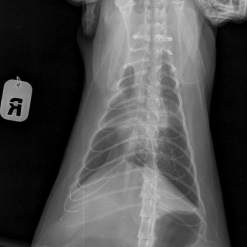

Срочный сбор на рентген 2 проекции 1400 руб. для Шурочки. ( завтра ).

Она сидит сгорбив спину ( больно), думали почки или печень.

А сегодня в клинике ее положили на спину и у нее начался жуткий кашель,

пришлось ставить укол от кашля. Похоже в нее стреляли ( как пулька на ребре прощупывается)

По рентгену пуль нет, а есть старый перелом грудины, небольшое количество жидкости в грудной области, очаговый ателектаз правого легкого, хр. бронхит, увеличена печень. В понедельник записались на УЗИ ( 600 руб.)